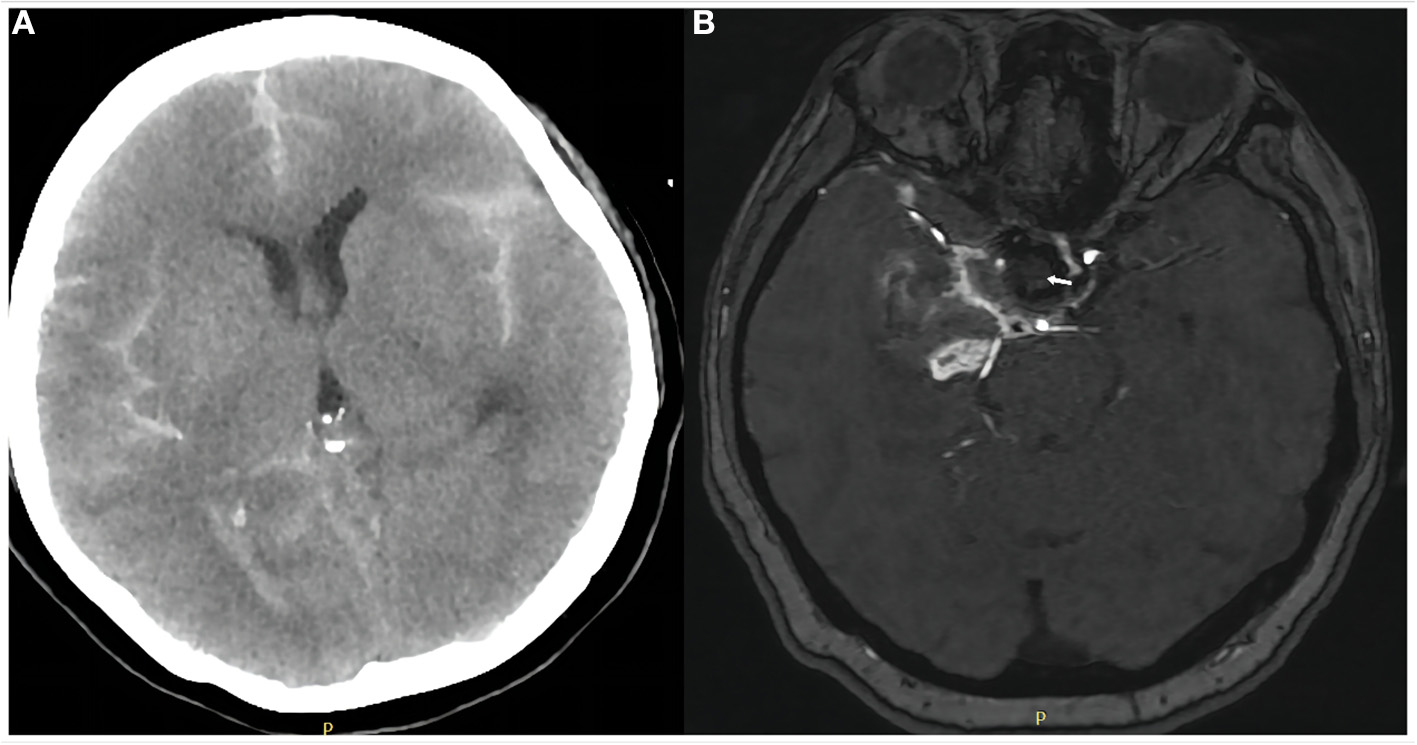

Figure 3

Anteroposterior (A) and lateral (B) views of cerebral angiography showed a small amount of blood flow into the aneurysm lumen (white arrows), suggesting delayed aneurysm rupture. Placement of a Willis covered stent (MicroPort, Shanghai, China) was then performed. Anteroposterior (C) and lateral (D) views of angiography performed immediately after the procedure showed no residual blood flow in the aneurysm lumen. The internal carotid and anterior choroidal arteries were patent.

Eleven hours after the procedure, the patient was found unresponsive. Emergency head CT showed SAH in the right Sylvian cistern, anterior interhemispheric fissure, and lateral ventricle (Hunt–Hess grade IV; modified Fisher grade 2; Figure 2B). Delayed aneurysm rupture was considered as the cause, and digital subtraction angiography showed that there was still a small amount of blood flow into the lumen of the aneurysm, suggesting the location of delayed aneurysm rupture here (Figures 3A,B). After a rapid discussion, the multidisciplinary team elected to proceed with endovascular placement of a WCS to completely isolate the aneurysm from the cerebral circulation.

The patient was extubated on the subsequent day after repeat head CT showed no progression of SAH (Figure 4A). Patients were asked to continue dual antiplatelet therapy (clopidogrel 75 mg/day and aspirin 100 mg/day) for at least 6 months after it was determined that the bleeding had stopped. Aspirin monotherapy was continued for life. Magnetic resonance angiography 6 days after treatment demonstrated parent artery patency and no aneurysmal filling (Figure 4B). The patient's left limb strength was grade 3 on manual muscle testing. She was transferred to a rehabilitation facility 1 week after WCS placement with modified Rankin scale score 2. However, we followed up with her by phone after 1 month and there were no new symptoms and the mRS score was 1, which was an improvement from the time of discharge.

Figure 4

Computed tomography of the head on day 1 after covered stent placement (A) showed no progression of subarachnoid hemorrhage or other obvious abnormality. Magnetic resonance angiography of the brain on day 6 (B) showed the aneurysm was completely occluded (white arrow) and the parent artery was patent.